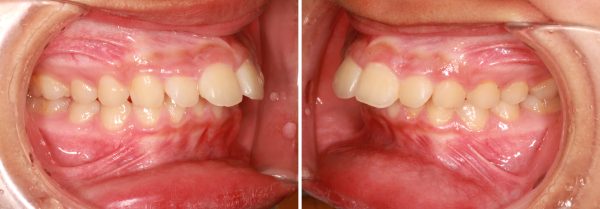

14歳の 女性です

「出っ歯、口もとを 治してほしい」との事で来院されました。

前歯が 飛び出しています。 典型的な ”出っ歯” の状態です

前歯 2本がより前に飛び出ていることが見た目をより悪くしています

前歯が 強く傾斜して、骨ごと 前に 出ています

上顎前突症(いわゆる 出っ歯)です

叢生を伴う 上顎前突症です